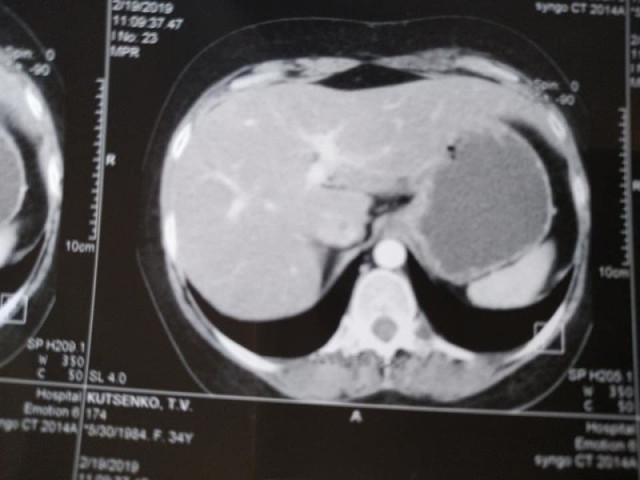

Тетяна – мама двох дітей. Нині жінка лікується препаратом "Ібранс", який дає хороший результат. За її словами, під час останнього КТ зафіксували зменшення пухлини у печінці.

"У мене метастази, 4 стадія, але постійна від початку лікування позитивна динаміка. З 5 пухлин різних за розмірами в печінці, залишилася одна 12 на 10мм, яка була на початку 50мм. На першому фото печінки видно плями темні-це вони,метастази,а на другому фото теперішній стан. Це дуже успішне лікування. Ще трішки і я надіюсь і ця пухлина теж зникне", – розповіла вона.